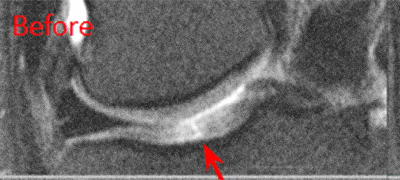

BEFORE And AFTER Imaging Results

Below are the outcomes of two patients with Regenexx protocol done for knee osteoarthritis. Scroll the arrow to the right to see the MRI of the knee joint before their treatment — the white/ lighter area indicates damage. Scroll to the left to see the MRI of the knee joint after their treatment.

Patient 2 MRI: 46 years old

- Patient 2: The patient had unsuccessful arthroscopic debridement surgery, where a large 3 cm. by 4 cm. osteochondral defect on the medial femur was discovered. The patient was then treated with percutaneously implanted autologous mesenchymal stem cells 1.5 years after surgery. The patient was able to return to full functional activities.